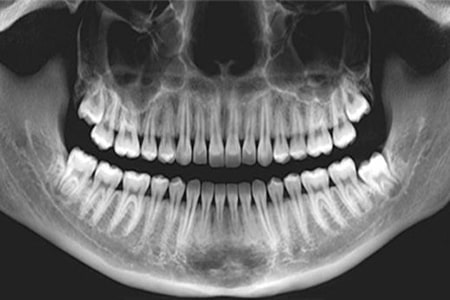

عکس او پی جی (OPG) مخفف عبارت ارتوپانتومونوگرام (Orthopantomogram) است که به آن (Panorex) هم می گویند، عکس opg دندان نوعی عکس اشعه ایکس دو بعدی از دندان ها و فک های بالا و پایین و اسکلت اطراف آن ها می باشد.

عکس او پی جی، نگاه پانورامیک از فک دارد در حالی که عکس سفالوگرام یک عکس اشعه ایکس از ساختارهای صورت است و عکس رادیولوژی معمولی دندان هم عکسی است که از ساختار یک یا چند دندان و کمی از بافت های اطراف آن گرفته می شود (که خود انواع گوناگون دارد).

- در این عکس تمامی دندانهای بالا و پایین در یک تصویر واحد دیده می شوند.

- در این تصویر، تعداد دندانها، موقعیت و زاویه آنها و هر گونه دندان نهفته در زیر لثه یا اضافی دیده می شود. به همین دلیل برای درمان ارتودنسی لازم است.

- او پی جی یا پانورامیک: تمامی محدوده دهان شامل همه دندانهای بالا و پایین را در یک عکس واحد نشان می دهد.

در عکس او پی جی همه دندانها و استخوان فک اطراف آنها در یک عکس دیده می شوند اما در عکس رادیولوژی معمولی، تنها یک یا چند دندان از زاویه نزدیک دیده می شوند. اگر چه این برای دیدن وضعیت دقیق تر یک دندان مشخص (مثلا وضعیت پالپ دندان یا آسیب دیدگی عصبهای داخل آن یا ترکهای ریز احتمالی) مفیدتر است اما برای دیدن نمای کلی دندانها مناسب نیست. با عکس او پی جی هر مشکلی در هر جایی از دهان که وجود داشته باشد دیده می شود. همچنین مشکلات مربوط به استخوان فک و ارتباط آن با سر و مفصل گیجگاهی فکی (مفصل فک) مشخص می شود. گاهی اوقات ممکن است لازم باشد هر دو نوع عکس اشعه ایکس گرفته شود.